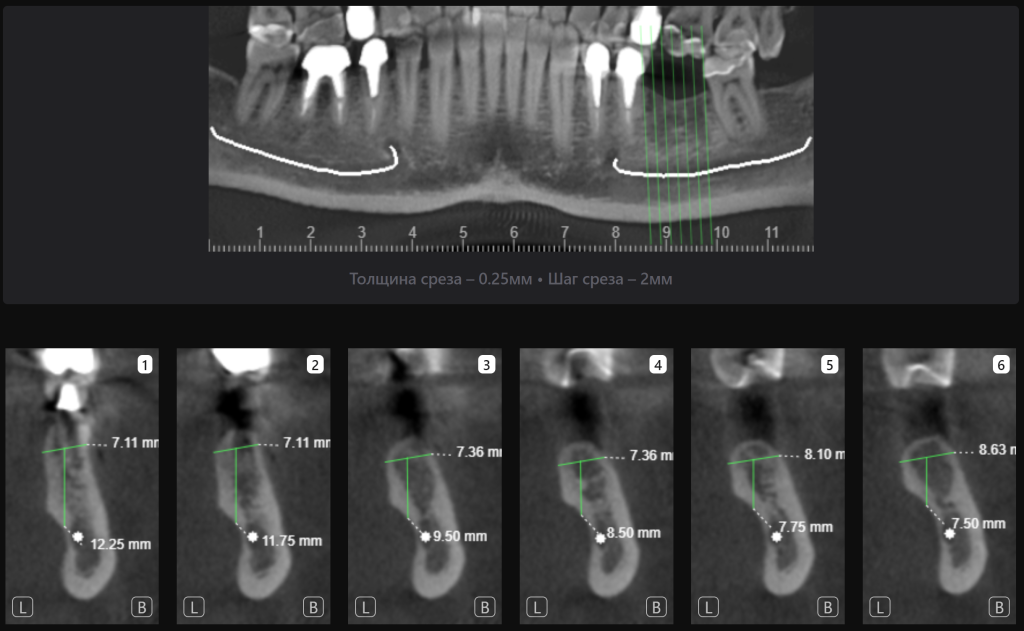

«Имплантологический отчет» Diagnocat способен автоматически измерить параметры костного гребня, помогая облегчить процесс выбора оптимальных размера и расположения имплантата